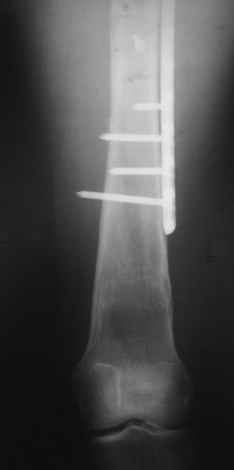

Re: Перелом проксимального отдела диспластичного б

Прошу прощения, со снимками глюк произошел. Высылаю. С уважением Евгений У.

Получилось очень симпатично, мои поздравления. А можно фото конечности без наклеек посмотреть?

И межфрагментарный винт на диафизе - так ли он нужен при выбранном варианте остеосинтеза с относительной стабильностью?

Хотя все-таки закрыто антгерадно заштифтовать тут было вполне можно, и при использовании отечетственного имплантата лечение обошлось бы на порядок дешевле. Опасения коллеги Кульджанова насчет кровоснабжения головки бедра и предстоящих операции в этой области кажуься несколько

преувеличенными - и стержень можно через вертел ввести, да и расстройства кровоснабжения головки, если они случатся после штифтования, не будут длиться вечно.

Но в люом случае, что сделано - то сделано, и сделанное выглядит вполне обнадеживающе, так что еще раз поздравляю коллег с успешным выходом из непростой ситуации.